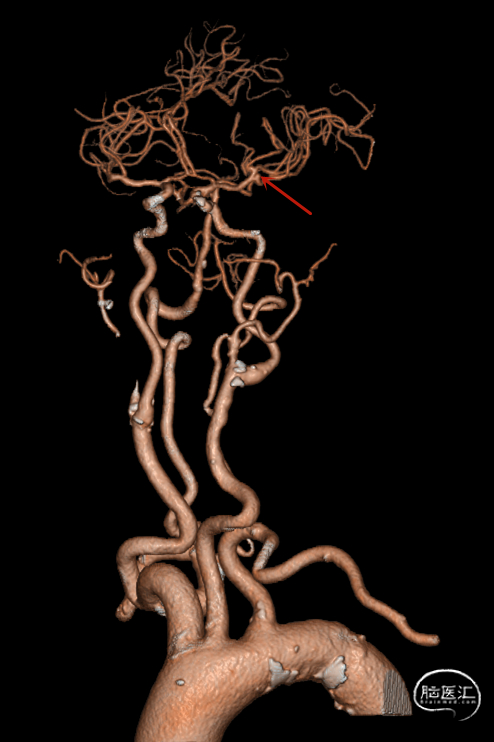

头部CTA,提示弓上血管迂曲,左侧大脑中动脉瘤(红色箭头):